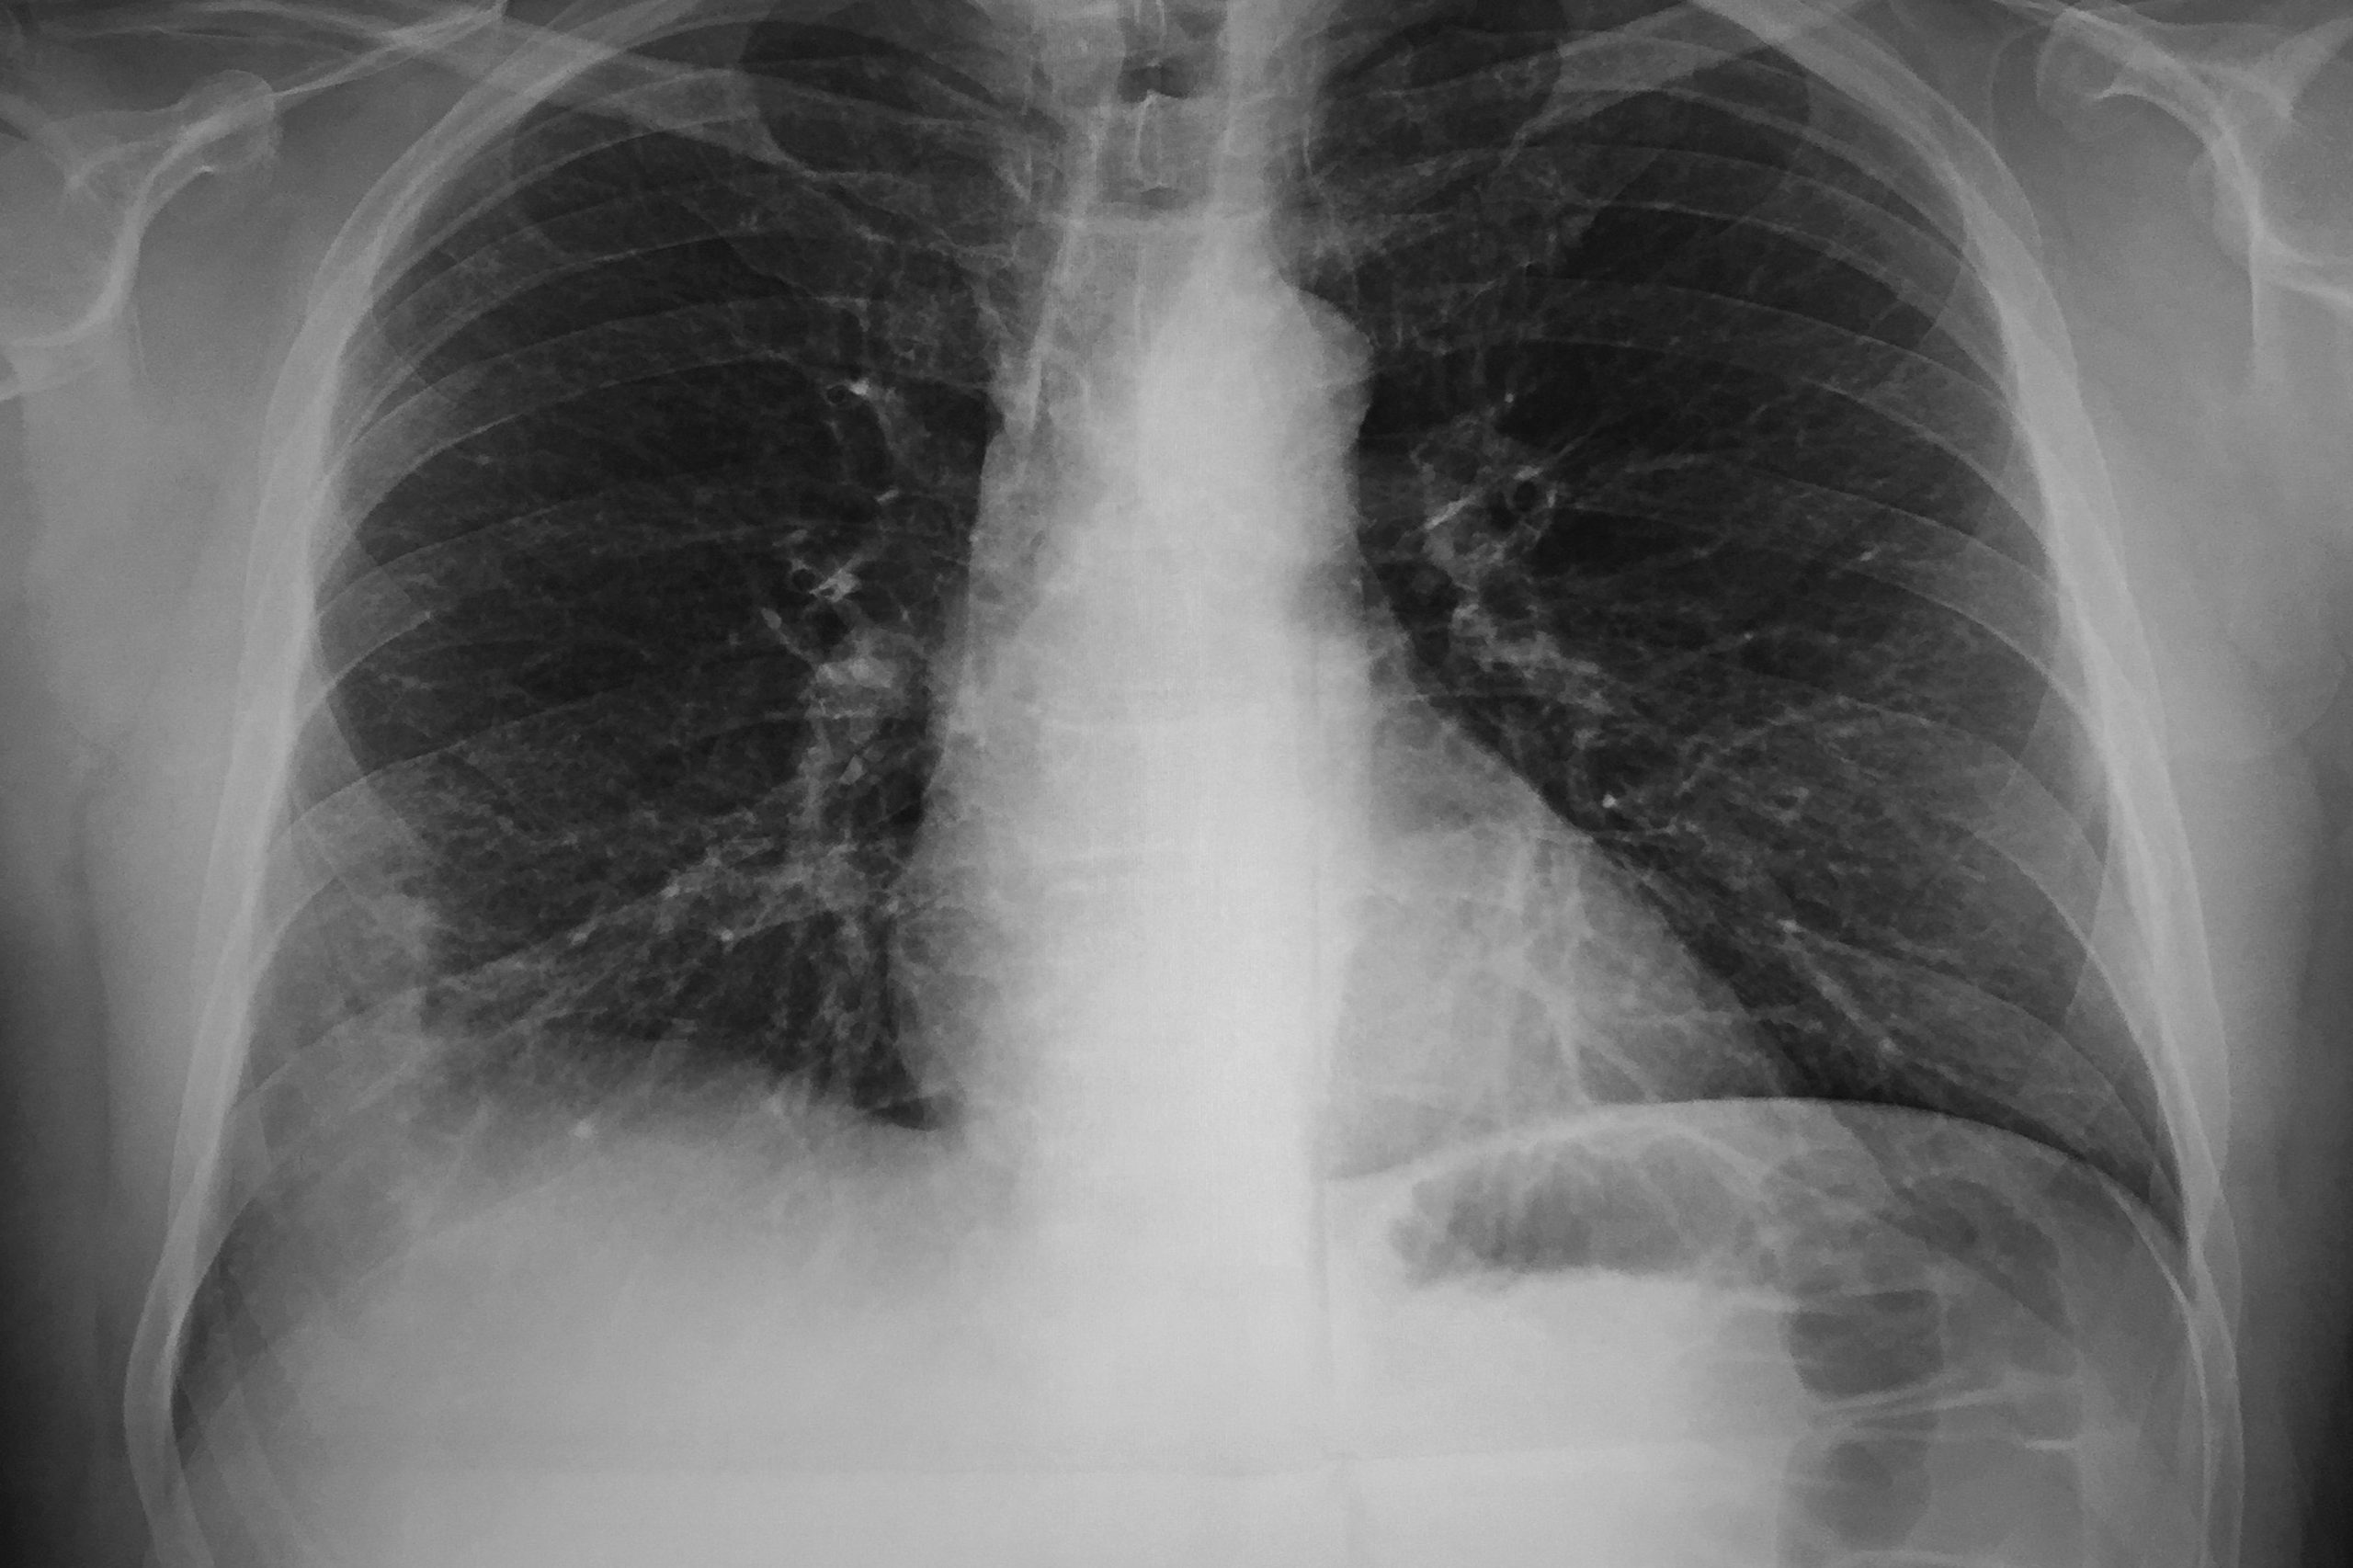

Cercetarea este publicată în revista Nature Materials. Bacteria Pseudomonas aeruginosa poate provoca o formă acută periculoasă de pneumonie. De obicei, aceasta este tratată cu antibiotice intravenoase, dar adesea acest lucru nu este suficient. Prin urmare, o astfel de pneumonie bacteriană are o rată de mortalitate destul de ridicată.

Oamenii de știință americani au creat nanoroboți pentru administrarea de medicamente. Aceștia constau din celule de alge a căror suprafață este acoperită cu nanoparticule. Aceste particule conțin antibiotice. Celulele de alge funcționează corect, astfel încât nanoroboții se pot deplasa și pot livra medicamentele la locul potrivit. Nanoparticulele care conțin antibiotice sunt realizate din polimer biodegradabil. Învelișul lor este, de asemenea, similar cu membrana neutrofilelor, un tip de celule albe din sânge. Datorită acestui fapt, nanoparticulele pot absorbi și neutraliza moleculele care provoacă inflamații și care sunt sintetizate de bacterii și de sistemul imunitar uman. Oamenii de știință au testat activitatea nanoroboților pe șoareci cu o formă periculoasă de pneumonie. Medicamentul a fost administrat prin intermediul unui tub plasat în trahee. Șoarecii și-au revenit în doar o săptămână și au trăit mai mult de 30 de zile, ceea ce reprezintă o rată de supraviețuire de 100%. Cu toate acestea, șoarecii netratați au murit în 3 zile.